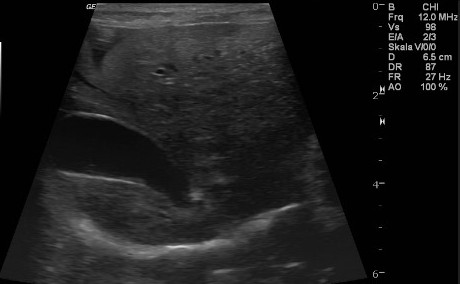

Niere und Harnableitendes System

Akute- und chronische Erkrankungen der Blase- und der Niere werden nicht selten unterschätzt. Einen Funktionsverlust der Nieren kann man im Akutfall nur mit sofortiger intensiver Therapie beheben und den chronischen Funktionsverlust nur Aufhalten jedoch selten noch ausheilen. Harnstoff und Kreatinin sind Funktionsparameter der Niere die erst verändert sind, wenn 80% des Nierengewebes bereits funktionslos geworden sind. Frühere Marker sind der SDMA-Marker und die UPC.

![]() |